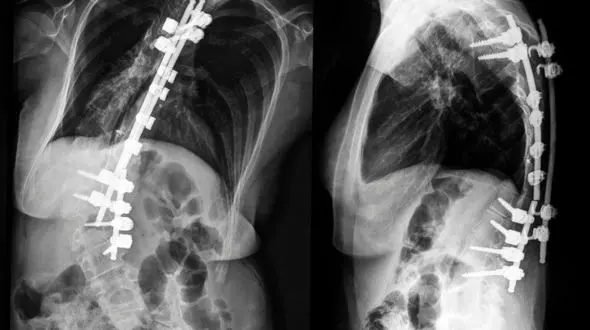

رکنا: اسکولیوز یک اختلال ساختاری در ستون فقرات است که موجب انحراف غیرطبیعی آن از راستای طبیعی میشود. در حالت عادی، ستون فقرات انسان باید به صورت یک خط مستقیم از پشت دیده شود. اما در افراد مبتلا به…